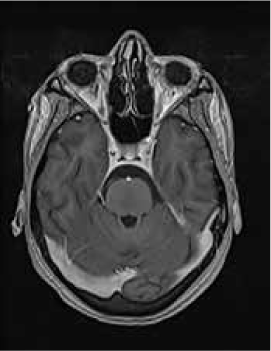

Magnetic resonance imaging (MRI) of the brain showed symmetrically increased T2-weighted and fluid-attenuated inversion recovery signal in the central pons (Figure 1) and in the striatum of the basal ganglia (Figure 2), with no contrast enhancement seen on corresponding T1-weighted postgadolinium images (Figures 3 and 4). Spinal MRI (Figure 5) demonstrated high signal on T2-weighted images from the area postrema in the medulla extending caudally to the T9 thoracic segment, with marked cord swelling and mild enhancement on T1-weighted postcontrast studies (Figure 6), in keeping with a longitudinally extensive inflammatory myelitis.

Magnetic resonance image of brain shows symmetrical, central high signal in pons on axial fluid-attenuated inversion recovery sequences

Postcontrast magnetic resonance image of brain show nonenhancing changes in pons

The clinical and radiologic features supported the diagnosis of NMO. However, the symmetrical pontine and basal ganglia high signal without contrast enhancement were considered to be strongly suggestive of concomitant ODS (pontine and extrapontine myelinolysis).

Neuromyelitis optica may lead to hyponatremia via at least two mechanisms. Area postrema involvement frequently causes intractable vomiting, and this may result in a low serum sodium level. Moreover, the syndrome of inappropriate antidiuretic hormone may develop in patients with NMO and hypothalamic lesions. In the present patient, the lowest recorded sodium level was 132 mmol/L. However, MRI demonstrated features of both central pontine and extrapontine myelinolysis, which, when occurring together, are considered virtually pathognomonic of ODS.4 Typical features include the symmetrical nature of the changes, the involvement of areas typically affected in ODS (pons, basal ganglia), and the sparing of peripheral pontine fibers. However, it remains a possibility that these radiologic changes were due to NMO primarily rather than osmotic demyelination. In a recent review, Kim et al.5 expanded on the range of MRI abnormalities consistent with NMO and NMO spectrum disorders. Gray matter demyelination of the thalamus and bilateral involvement of the corticospinal tracts have been described, although published examples are not as strikingly symmetrical as in this case and do not show the combination of central pontine demyelination with symmetrical striatal involvement.5 To our knowledge, these typical ODS changes in the context of NMO have been described in only one other case, in the Japanese literature.6